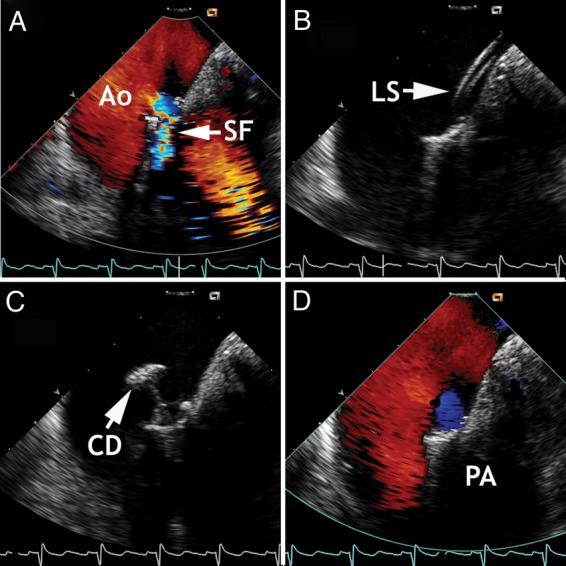

Current interventional procedures in structural heart disease and cardiac arrhythmias require peri-interventional echocardiographic monitoring and guidance to become as safe, expedient, and well-tolerated for patients as possible. Intracardiac echocardiography (ICE) complements and has in part replaced transoesophageal echocardiography (TEE), including real-time three-dimensional (RT-3D) imaging. The latter is still widely accepted as a method to prepare for and to guide interventional treatments. In contrast to TEE, ICE represents a purely intraprocedural guiding and imaging tool unsuitable for diagnostic purposes. Patients tolerate ICE much better, and the method does not require general anaesthesia. Accurate imaging of the particular pathology, its anatomic features, and spatial relation to the surrounding structures is critical for catheter and wire positioning, device deployment, evaluation of the result, and for ruling out complications. This review describes the peri-interventional role of ICE, outlines current limitations, and points out future implications. Two-dimensional ICE has become a suitable guiding tool for a variety of percutaneous treatments in patients who are conscious or under monitored anaesthesia care, whereas RT-3DICE is still undergoing clinical testing. Continuous TEE monitoring under general anaesthesia remains a widely accepted alternative.

目前,结构性心脏病和心律失常的介入治疗需要围介入期超声心动图监测和引导,以使患者尽可能安全、便捷且耐受性良好。心内超声心动图(ICE)补充并部分取代了经食管超声心动图(TEE),包括实时三维(RT-3D)成像。后者仍被广泛认可为一种用于准备和引导介入治疗的方法。与TEE不同,ICE是一种纯粹的术中引导和成像工具,不适合用于诊断目的。患者对ICE的耐受性要好得多,且该方法不需要全身麻醉。对特定病变及其解剖特征以及与周围结构的空间关系进行准确成像,对于导管和导丝定位、器械部署、结果评估以及排除并发症至关重要。本综述描述了ICE在围介入期的作用,概述了当前的局限性,并指出了未来的意义。二维ICE已成为清醒或接受麻醉监测的患者进行各种经皮治疗的合适引导工具,而实时三维心内超声心动图(RT-3DICE)仍在进行临床试验。全身麻醉下持续的TEE监测仍然是一种广泛接受的替代方法。